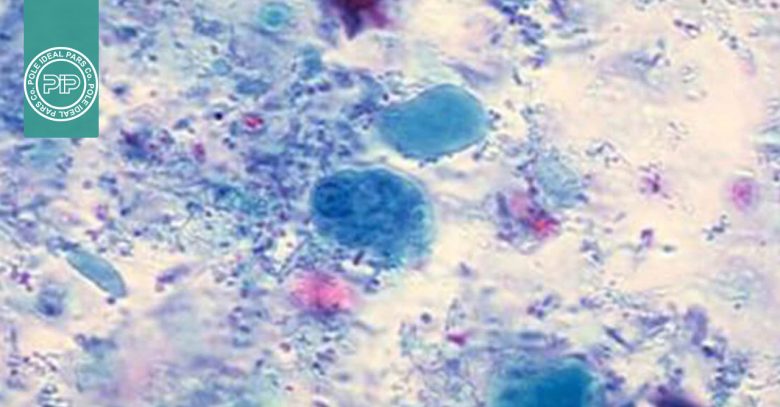

نتایج و تفسیر رنگآمیزی تریکروم ویتلی

نتایج رنگ آمیزی تریکروم ویتلی به صورت زیر خواهد بود:

- مشاهده پروتوزوآها: تروفوزوئیتها و کیستهای پروتوزوآ باید زیر میکروسکوپ بررسی شوند.

- رنگآمیزی سیتوپلاسم تروفوزوئیتها: معمولاً آبی-سبز یا بنفش روشن دیده میشود.

- رنگآمیزی کیستها:کیستها رنگ بنفشتر دارند.

- مشاهده سلولهای انسانی و مخمر: سلولهایی مانند گلبولهای قرمز (RBCs)، پلیمورفونوکلئرها (PMNs)، ماکروفاژها و همچنین مخمرها میتوانند شناسایی شده و به رنگ قرمز دیده شوند.

- هستهها و اجسام داخل سلولی: هستهها و inclusion bodies نیزرنگ قرمز با تهرنگ بنفش به خود میگیرند.

- پسزمینه : پسزمینه رنگ سبز دارد و این باعث کنتراست بالا با پروتوزوآها میشود.

- گلیکوژن: مولکولهای گلیکوژن توسط حلالهای رنگ حل میشوند و به صورت شفاف و بدون رنگآمیزی دیده میشوند، درست مانند خود ارگانیسم.